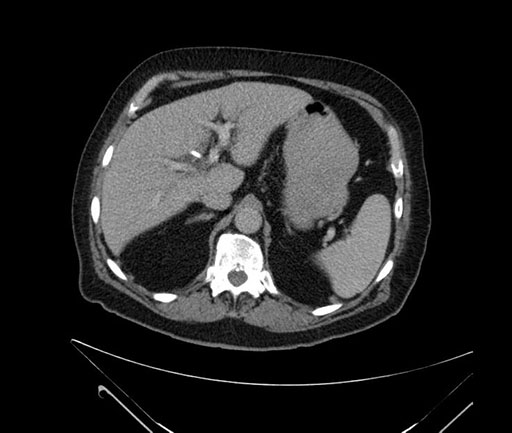

Whipple (pancreaticoduodenectomy) [case 7]

Coronal - stented